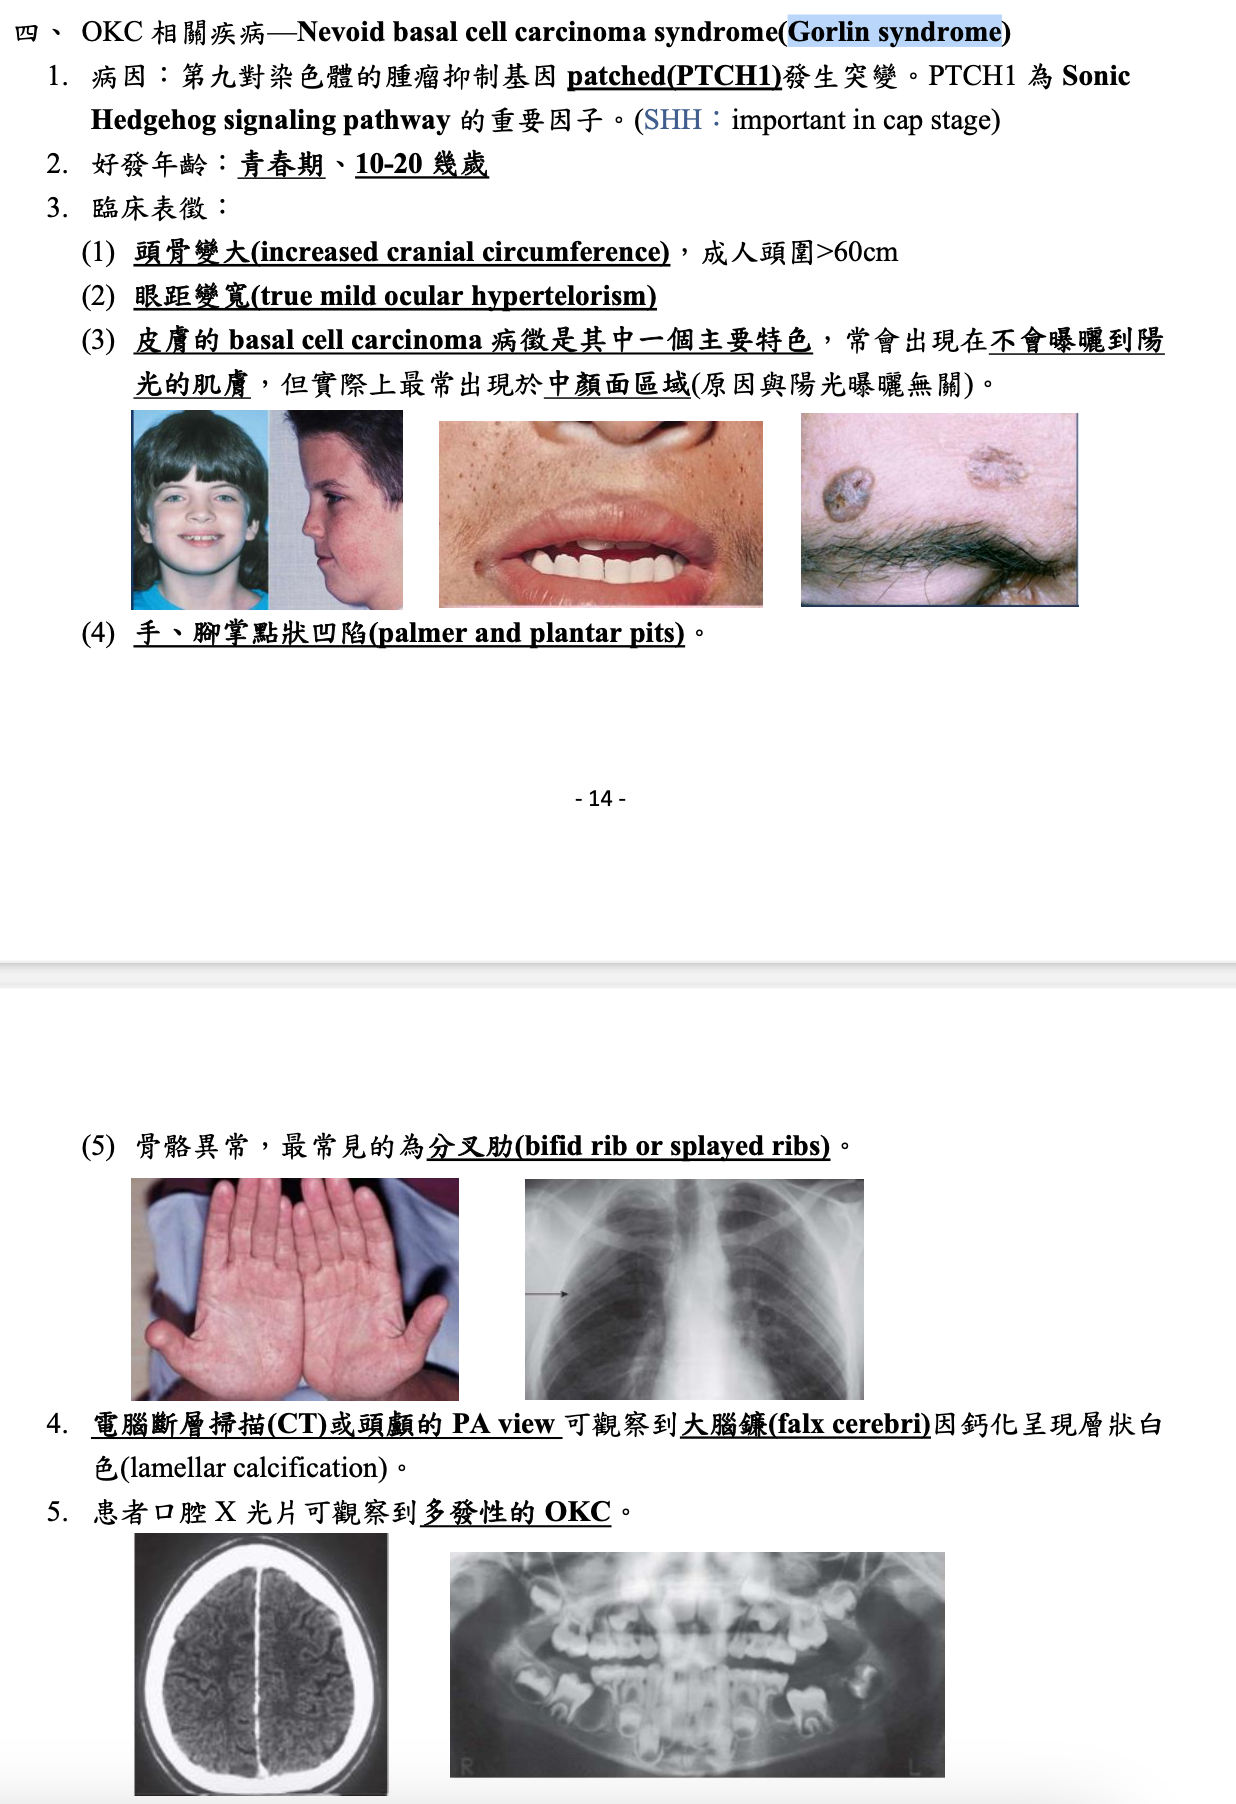

Gorlin syndrome

- SUFU 也可能造成

Epidermoid Cyst (Infundibular cyst) |

| Gorlin syndrome | 多發性 | |||